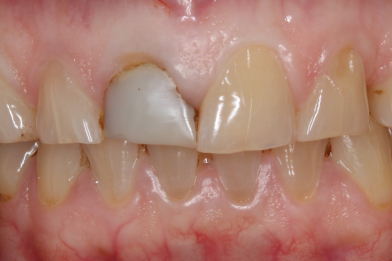

Реставрация верхних резцов с закрытием диастемы

Евсеенкова Дарья Эдуардовна -